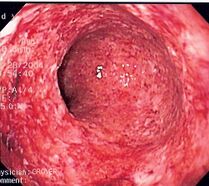

الالتهاب الحاد هو أول استجابة دفاعية للجسم للإصابة أو المرض. الاستجابة تقودها الخلايا المناعية مثل العدلات والحمضات. يمكن أن يرتبط الالتهاب الحاد بالعدوى أو الإصابة الرضحية أو أمراض المناعة الذاتية (مثل التهاب المفاصل الروماتويدي) أو السرطان. على الرغم من أن الالتهاب الحاد هو جزء مهم من نظام الدفاع في الجسم، إلا أن الالتهاب الحاد المطول يمكن أن يتسبب في إصابة الأنسجة المصابة. تظهر هذه الأنواع من التغييرات بشكل شائع في الجلد والفم والجهاز الهضمي (المريء والمعدة والأمعاء الدقيقة والقولون).[1]

قد يقوم الطبيب بإزالة قطعة صغيرة من الأنسجة في إجراء يسمى الخزعة وإرسالها إلى أخصائي علم الأمراض للبحث عن التهاب حاد. من خلال فحص الأنسجة تحت المجهر، سيتمكن أخصائي علم الأمراض أيضًا من استبعاد الحالات الأخرى التي يمكن أن تبدو مثل الالتهاب مثل السرطان.

- إلتهاب القولون المؤلم والمصاحَب بإسهال، قد ينتج عن؛

-اعتداء جرثومي (كبكتيريا السّالمونيلاّ) أو طفيلي (كالأميبا)..، -اعتداء تخمّري أو تفسّخي للموادّ العضوية من طرف أمّة الجراثيم, الـرِّمِّـية، -أو اعتداء بسموم غذائية؛ أغذية غير طاهرة (خضراوات وفواكه لم تغسل أو أغذية بائتة.. أو أغذية لم تحفظ جيدا, أو أطعمة تداولتها أيدي ملوّثة..).